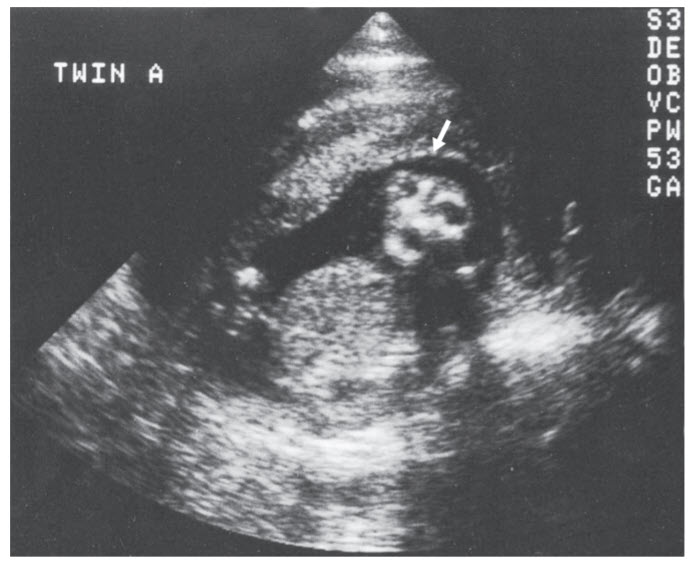

The sonographic image was done at approximately 15 weeks’ gestation and shows two orbits, a mouth, and a central nose, but there is clearly no forehead and no cranial contents. Anencephaly is incompatible with life.